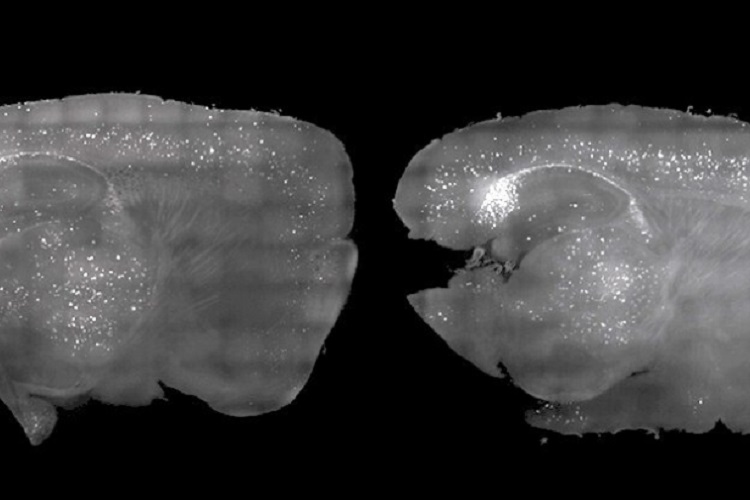

This noninvasive treatment also greatly reduced the number of amyloid plaques found in the brains of these mice. Plaques were cleared in large swaths of the brain, including areas critical for cognitive functions such as learning and memory.

“When we combine visual and auditory stimulation for a week, we see the engagement of the prefrontal cortex and a very dramatic reduction of amyloid,” said Li-Huei Tsai, one of the researchers from MIT’s Picower Institute for Learning and Memory.